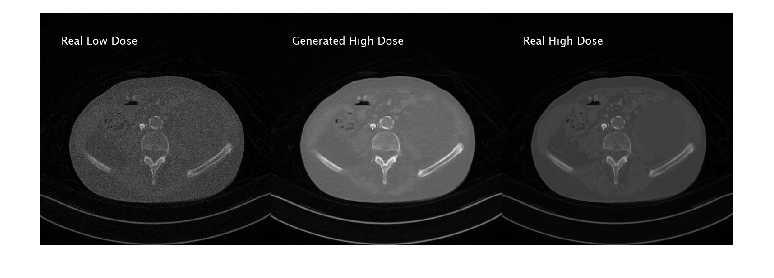

Generate New Images Using Test Data

Define the number of test images to use for calculating quality metrics. Randomly select test images to display.

numImagesToDisplay = 3;

idxImagesToDisplay = randi(numel(filesTestHD),1,numImagesToDisplay);

for idx = idxImagesToDisplay

dsTestHD = partition(timdsTestHD,Files=idx);

imageHD = read(dsTestHD);

imageHD = imageHD{1};

dsTestLD = partition(timdsTestLD,Files=idx);

imageLD = read(dsTestLD);

imageLD = imageLD{1};

imageLD = dlarray(imageLD,"SSCB");

if canUseGPU

imageLD = gpuArray(imageLD);

end

% Generate high-dose image from low-dose image

imageHDGenerated = predict(genLD2HD,imageLD);

imageHDGenerated = gather(extractdata(imageHDGenerated));

imageLD = gather(extractdata(imageLD));

imageResultsLDReal = insertText(rescale(imageLD),[40 40],"Real Low Dose", ...

FontSize=24,TextColor="white",BoxOpacity=0);

imageResultsHDGen = insertText(rescale(imageHDGenerated),[40 40],"Generated High Dose", ...

imageResultsHDReal = insertText(rescale(imageHD),[40 40],"Real High Dose", ...

figure

montage({imageResultsLDReal,imageResultsHDGen,imageResultsHDReal},Size=[1 3]);